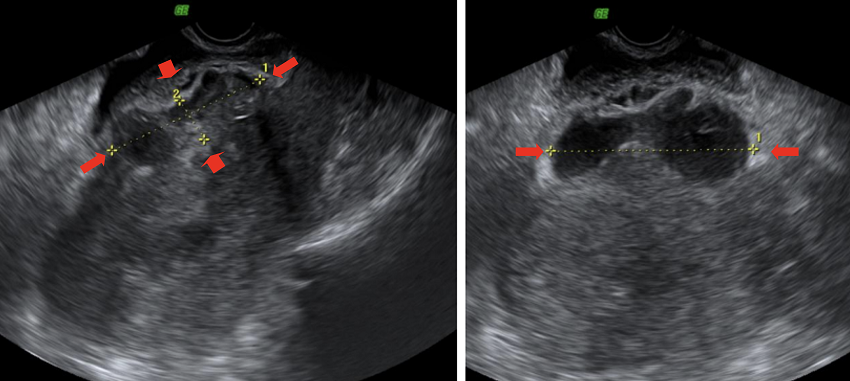

Al ingreso, el uroanálisis mostró un recuento de leucocitos de 500 num//xl, proteínas 100 mg/dl y 1774 leucocitos/campo; en el hemograma los leucocitos fueron 8960//xl, neutrófilos 6.320//xl, hemoglobina 9,4 g/dl, hematocrito 28,6 %, plaquetas 390100/ul; en la bioquímica destacaba proteína C reactiva 40,3 mg/L. Con estos hallazgos, el diagnóstico más probable era una infección urinaria baja, sin poder descartar otras causas de dolor abdominal, dado el antecedente de una cirugía reciente. Al realizar ecografía transvaginal se visualizaba útero en anteversión con endometrio irregular de 2 mm con posibles restos hemáticos en su interior y con una formación heterogénea a nivel de la cicatriz de la cesárea compatible con un hematoma de 66 x 18 x 81 mm. Los ovarios eran normales y no había líquido libre abdomino-pélvico (Figura 1 a y b).